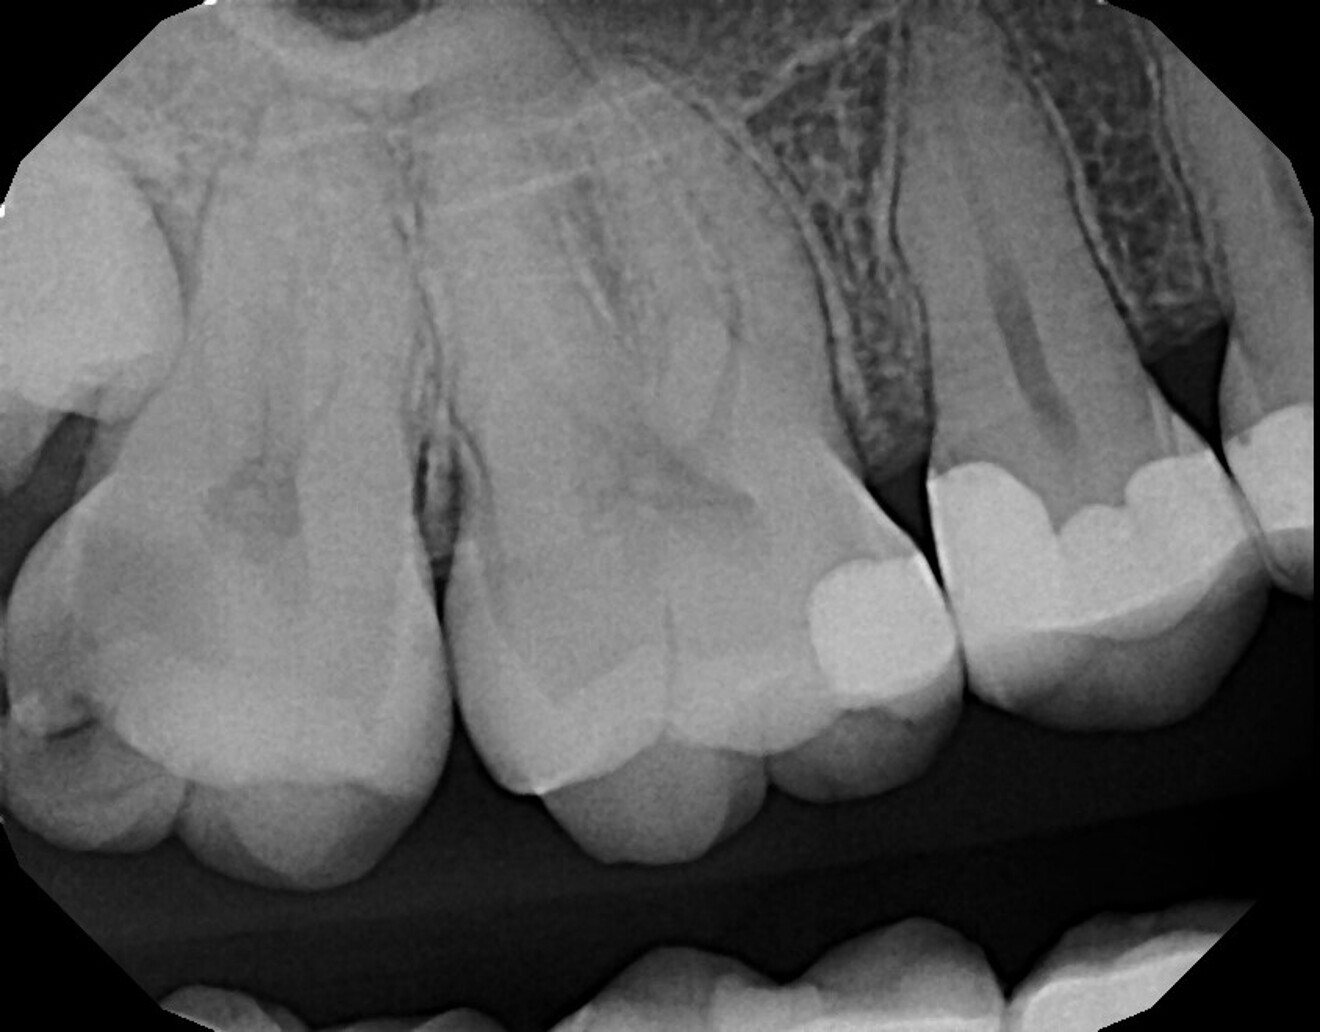

A 34-year-old female patient presented with the complaint of pain and temperature sensitivity in the maxillary right posterior. Clinical examination noted caries on the distal aspect of the second molar, and a periapical radiograph was taken (Fig. 10). Deep caries was confirmed radiographically on the disto-occlusal aspect of tooth #17 that was very close to the pulp, but a lack of periapical pathology was noted. The tooth was tested with cold to verify that the pulp was vital. A mild reaction was noted when cold was applied that immediately resolved when cold was removed from the tooth, indicating that the tooth was vital. The patient was informed that pulpal exposure would most likely result from caries removal and endodontic treatment may thus be necessary or become necessary at a later date after treatment. Treatment would consist of laser pulpal treatment should a large exposure not result, followed by a core build-up and restoration with a complete crown. The patient agreed to the recommended treatment.

The patient was seen at routine prophylactic recall appointments, and at the five-year recall appointment, a periapical radiograph was taken (Fig. 12). As was noted in prior follow-up radiographs, no periapical radiolucency was seen, demonstrating that the laser treatment had been successful in preventing periapical pathology and pulpal infection.

Fig. 10: Periapical radiograph taken preoperatively, demonstrating deep caries on the disto-occlusal aspect and minimal tooth substance over the pulp.

Fig. 12: Periapical radiograph five years after laser pulpal treatment and restoration of the tooth, demonstrating no periapical pathology.